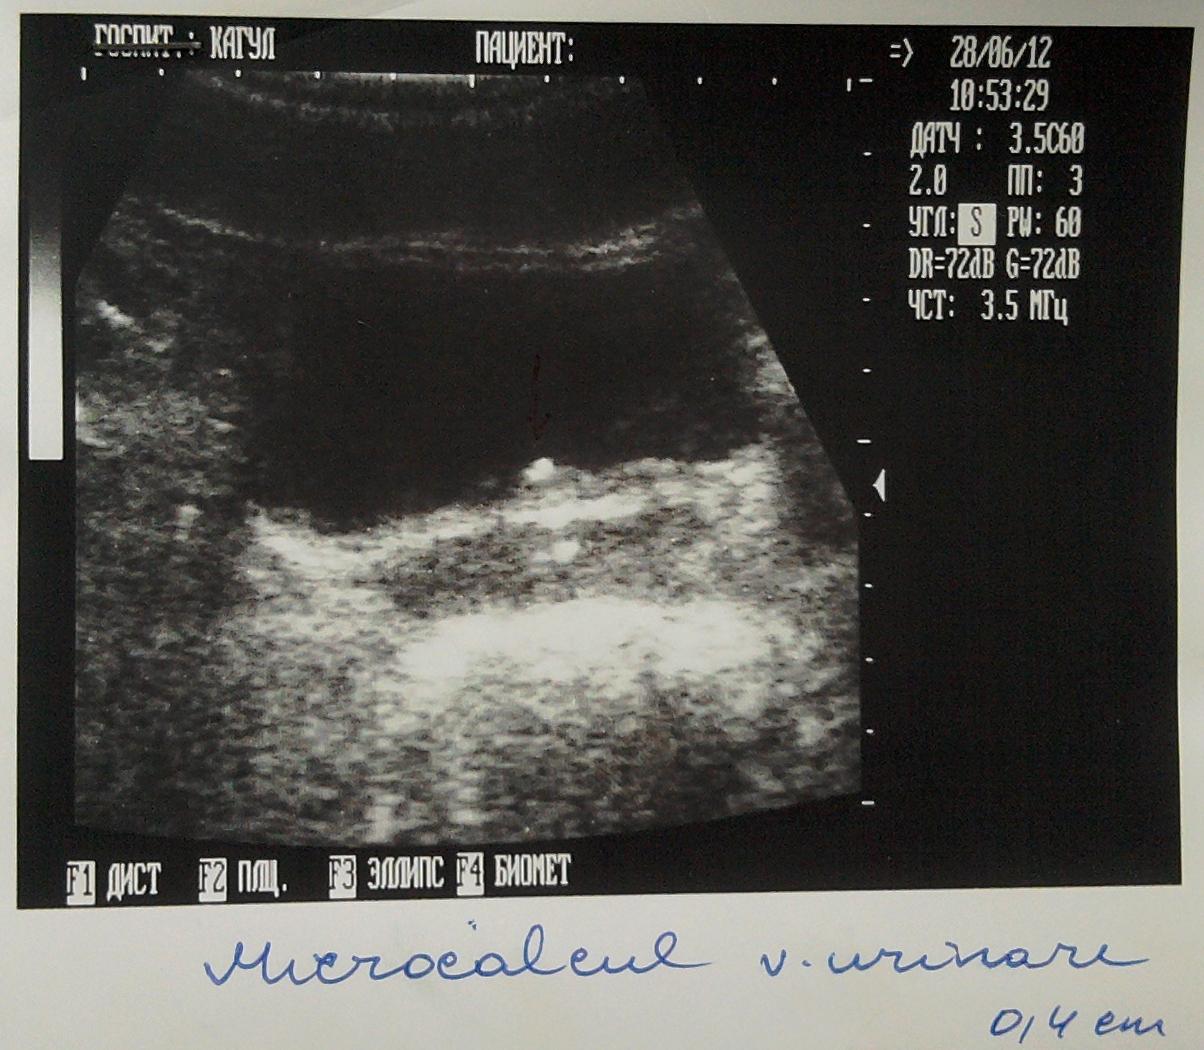

Возможно ли что у меня в мочевом пузыре кальцинат размером 0,4см

Здравствуйте я зделал год назад узи мочевого пузыря и у меня обнаружили камушек размером в 0,4 см, потом я посетил местного уролога он назначил мне Шилинтонг по 3 таблетки 3 раза в день. Я иногда по 4 пил.

- Через пол года я опять зделал узи и камушек как стоял так и стоит, после этого я пошол к врачу он решил что они видят не камушик а что-то с простатой и взял анализ( анализ нормальный как он мне сказал ) и сказал что это наверное кальцинат и не надо не какого личения. Чтоб я опять через пол года зделал узи.

Вот я и хочу узнать может я мало таблеток Шилинтонга пил или это действительно кальцинат и что с этим делать???

Ниже я прикрепил фото узи.

Такого размера кальцинат должен отойти незамеченным из мочевого пузыря. Сделайте МСКТ почек, мочеточников , мочевого пузыря и простаты.